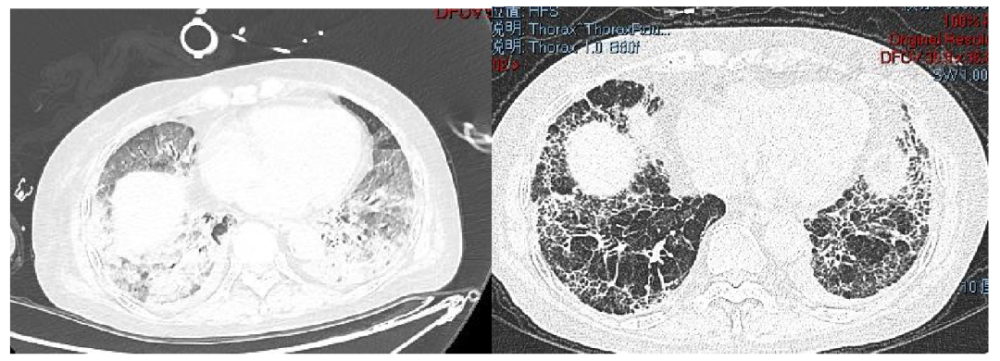

肺纖維化高發(fā)

《Nature Medicine》2021年發(fā)表了“Post-acute COVID-19 syndrome”,研究指出呼吸困難在60-100天的隨訪期內(nèi)的發(fā)生率為42%-66%,有6.6%的患者因持續(xù)低氧血癥需要補(bǔ)充氧氣。患者出院后3個月評估發(fā)現(xiàn)約25%的輕度至中度病例存在纖維化,在重癥病例居多的隊列中,約65%的康復(fù)者存在肺纖維化。